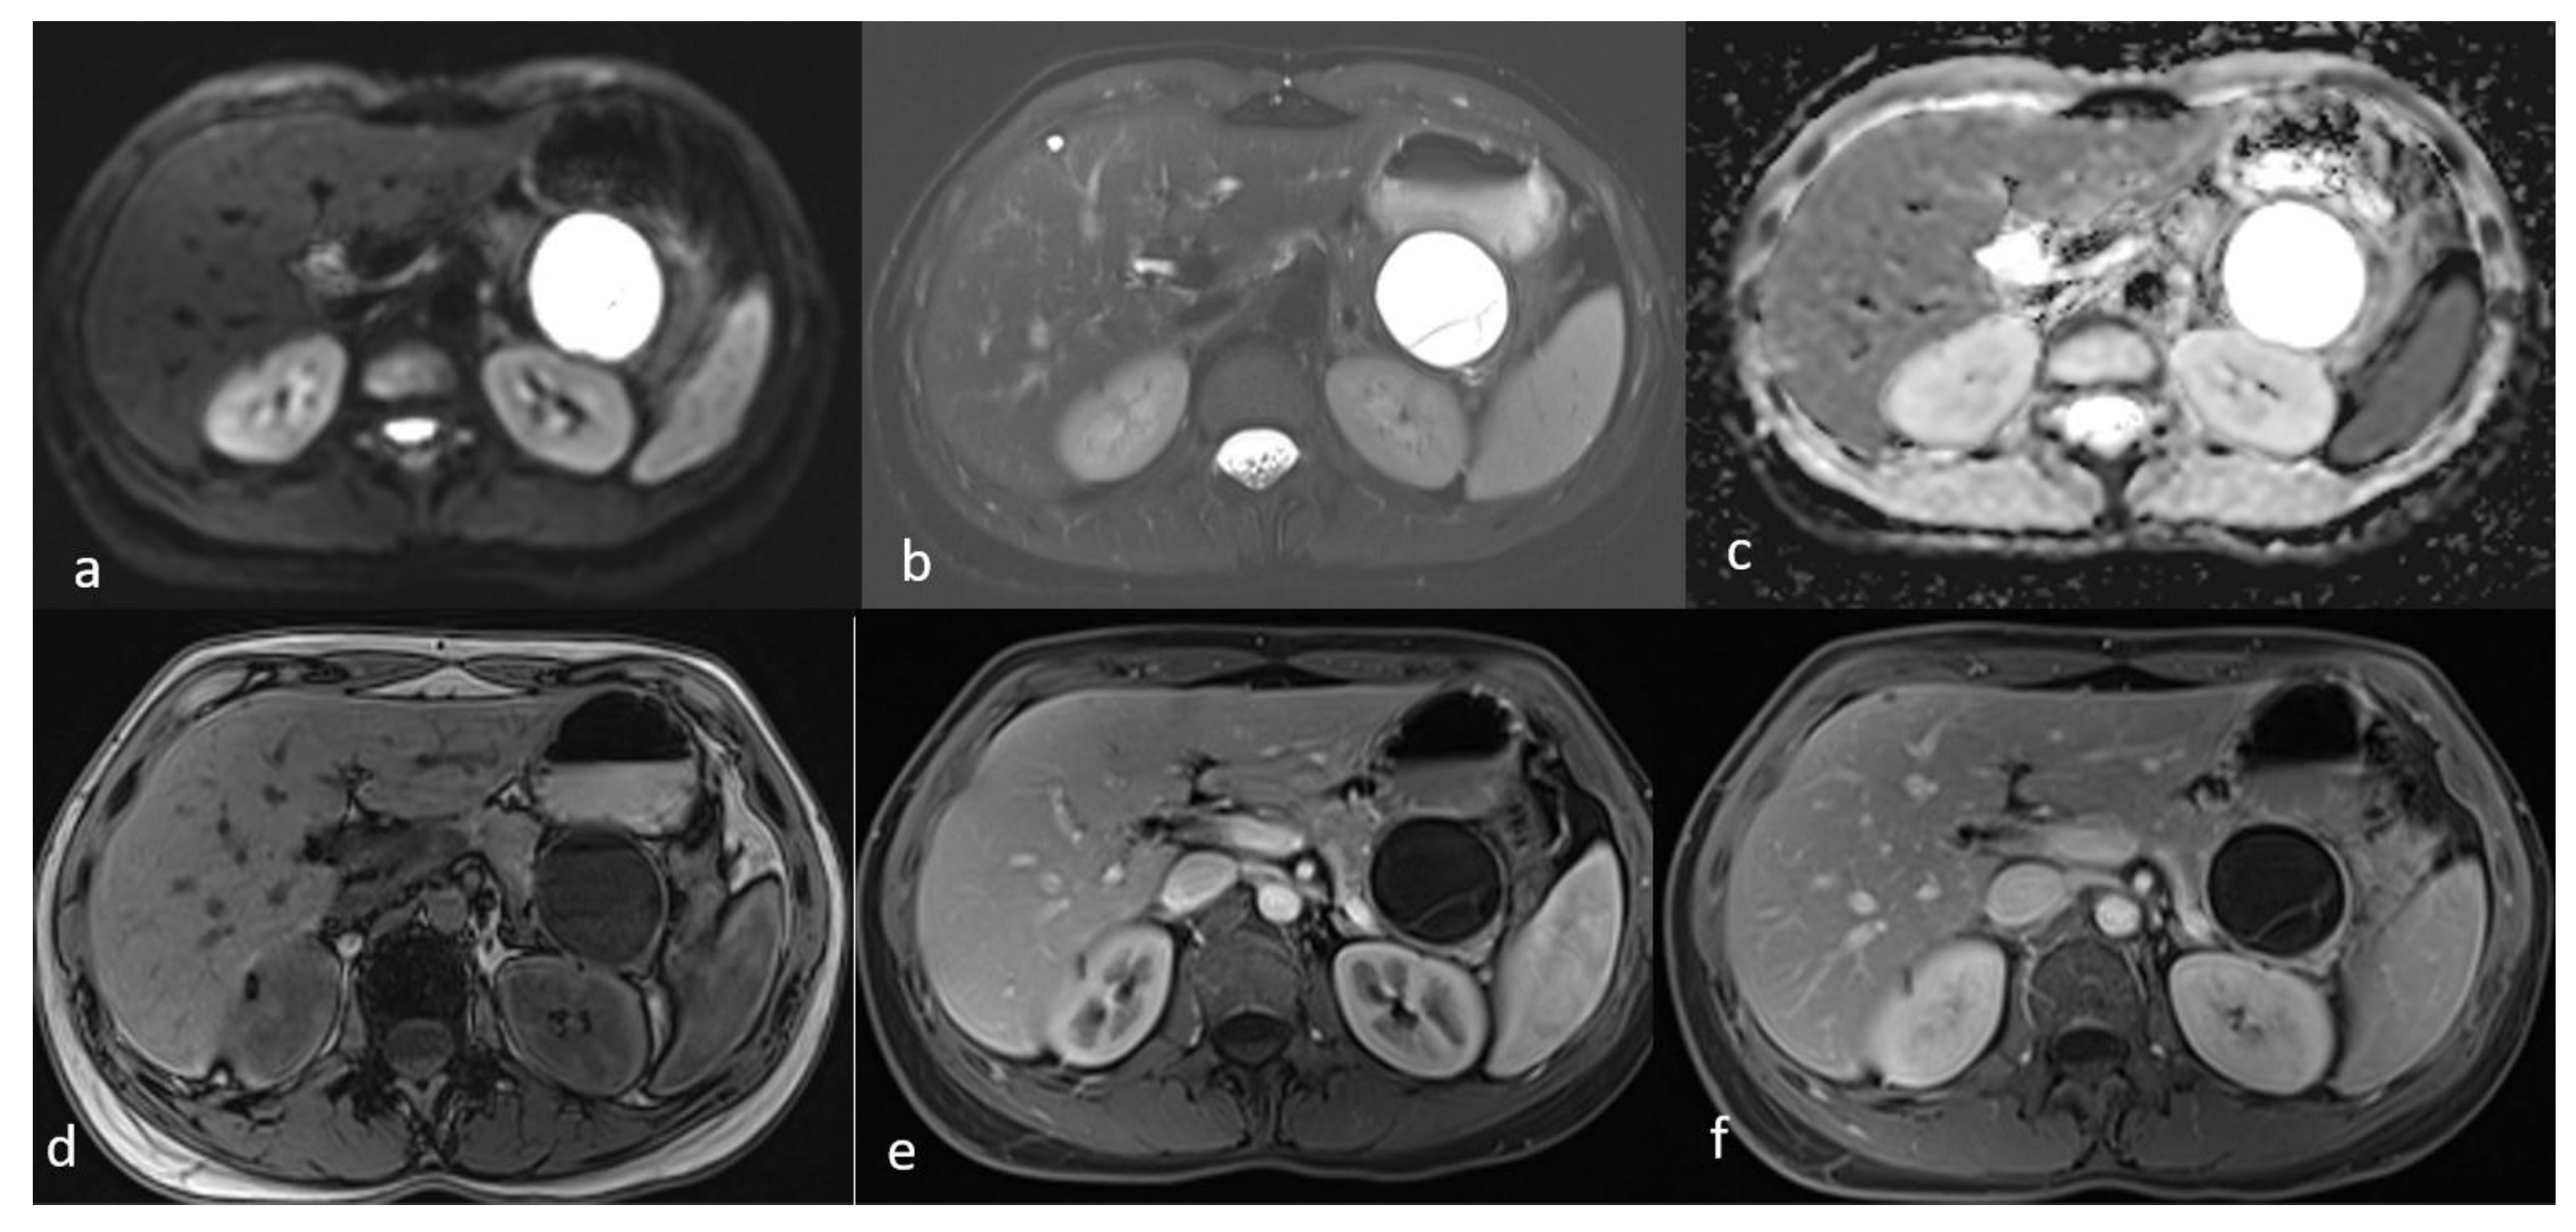

An MRI performed one year after the initial imaging and two months before admission revealed an increase in the size of the pancreatic cystic lesion to 4.5 cm (Figure 3 and Figure 4) with enhancement of its thin wall and internal septa, confirming its progressive nature. The lesion continued to compress the pancreatic tail and the greater curvature of the stomach, without causing pancreatic duct dilation. The imaging also showed low signal intensity on T1- and high signal intensity on T2-weighted sequences, with capsule enhancement post-contrast, suggesting a mucinous cystic neoplasm (Figure 4). Additionally, the MRI confirmed the presence of a 9 mm hemangioma and a small liver cyst, both unchanged from prior scans. No enlarged retroperitoneal lymph nodes were observed, and the MRCP findings showed normal intrahepatic bile ducts, common hepatic bile duct, gallbladder, and pancreatic duct. No abnormalities were found in the spleen, kidneys, or adrenal glands.

Figure 4.

Second MRI follow-up after 6 months showed an increase in the lesion size. (a) T2 Blade axial sequence showing hyperintensity of the cyst with no internal solid component. (b,c) DWI and ADC again showing no internal restriction of the cystic lesion. (d) T1 Vibe showing a hypointense cystic lesion at the tail of the pancreas. (e,f) T1 Vibe post-contrast at arterial and venous phases showing no change in the enhancement of the cyst.